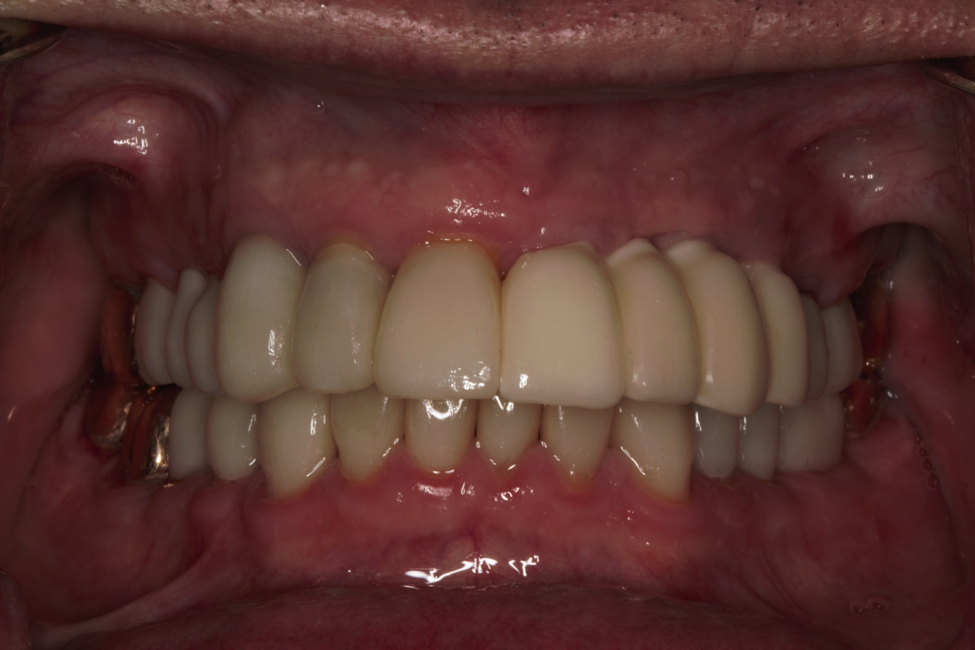

This patient came to us with several completely worn teeth. He also had some teeth missing. We had to do several things to ensure we could make him teeth that looked and felt normal. He had to undergo both periodontal surgery and implant surgery. We then restored his smile with crowns and implant crowns. He loves his new teeth.